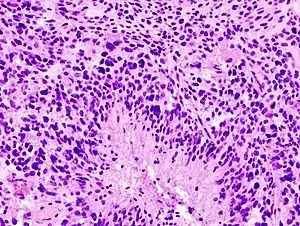

![]() Гістологічний зріз гліобластоми Гістологічний зріз гліобластоми | |